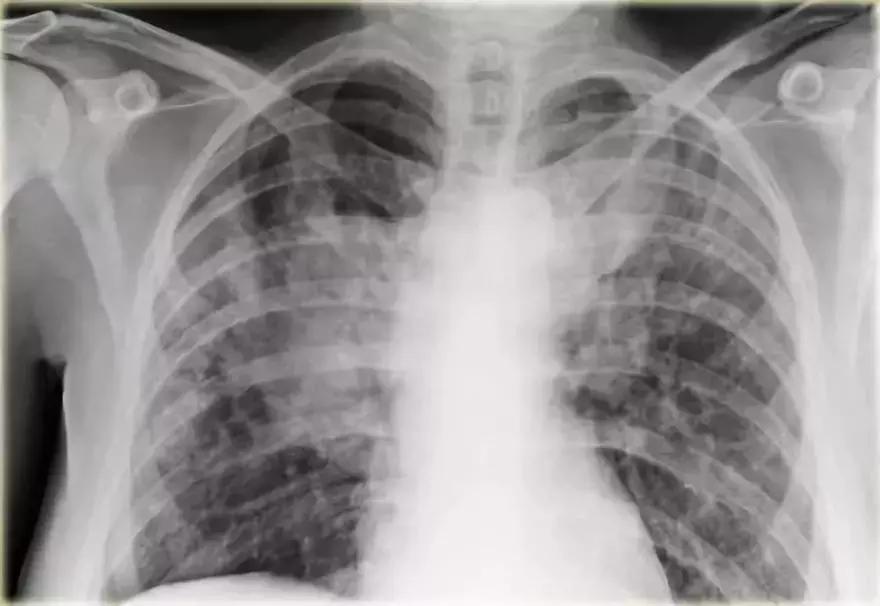

充血性心力衰竭

影像学信息:

➢ 双侧肺门实变,伴有空气-支气管征及边界模糊

➢ 心脏大小增加

➢ 间质轻微肺纹

➢ 血管蒂可能增大

图10 充血性心力衰竭